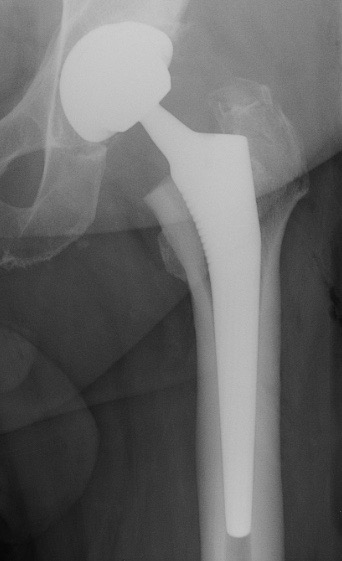

A. PTH avec double mobilité